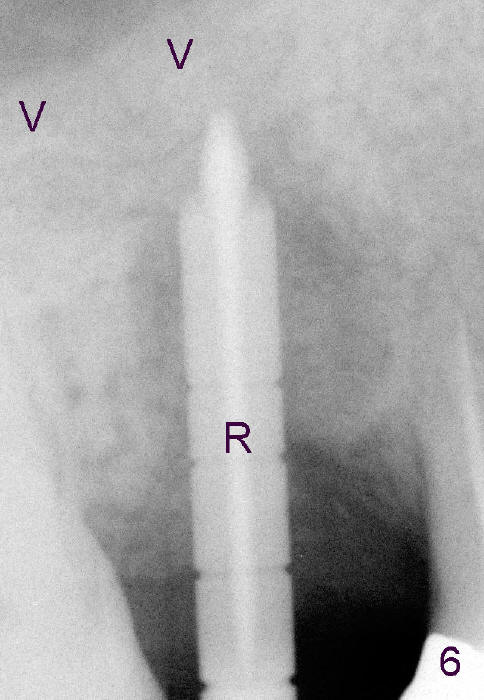

A few months after cementation of implant (Fig.1 I) crown (C) at #30, a 44-year-old man fractured the tooth #4 with MOD amalgam (S) and root canal thereapy (<) while he was visiting his home country. Fig.2 shows the socket (black arrowheads) and bony defect (white arrowheads).

Osteotomes are used to form initial osteotomy, approximately 11 mm deep, 4 mm wide. Bicon reamers (Fig.3 R) are used to increase osteotomy while collecting autogenous bone; it appears that the sinus floor is partially penetrated (dashed line). After sinus lift (Fig.4 dashed line), a 5x14 mm cylindrical tissue-level implant is placed (I; arrowheads: sinus floor). There is no intraop nasal hemorrhage. Amoxicillin is prescribed postop (500 mg tid for 7 days). There is purulent, particulate discharge from the right nostril postop. One month later, the implant is loose and removed.

Four months after implant removal, the bony defect appears to increase (Fig.5). Reamers (Fig.6 R)and osteotome (Fig.7 O) are short of the sinus floor (arrowheads). A 5x14 mm tapered implant is placed with primary stability (Fig.8 I). The implant is placed ~ 2 mm deeper (Fig.9). No bone graft is used for sinus lift. There is no complication. The sinus floor appears to be repaired 4.5 months postop (Fig.10). Fig.11 (trimmed from panoramic X-ray) is taken 1 year 7 months post cementation. The bone remains stable 4 years 2 months post cementation (Fig.12); the mesial defect is most likely related to extraction trauma (*).